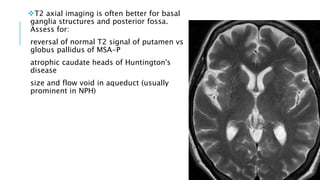

T2 axial imaging is often better for basal

ganglia structures and posterior fossa.

Assess for:

reversal of normal T2 signal of putamen vs

globus pallidus of MSA-P

atrophic caudate heads of Huntington's

disease

size and flow void in aqueduct (usually

prominent in NPH)